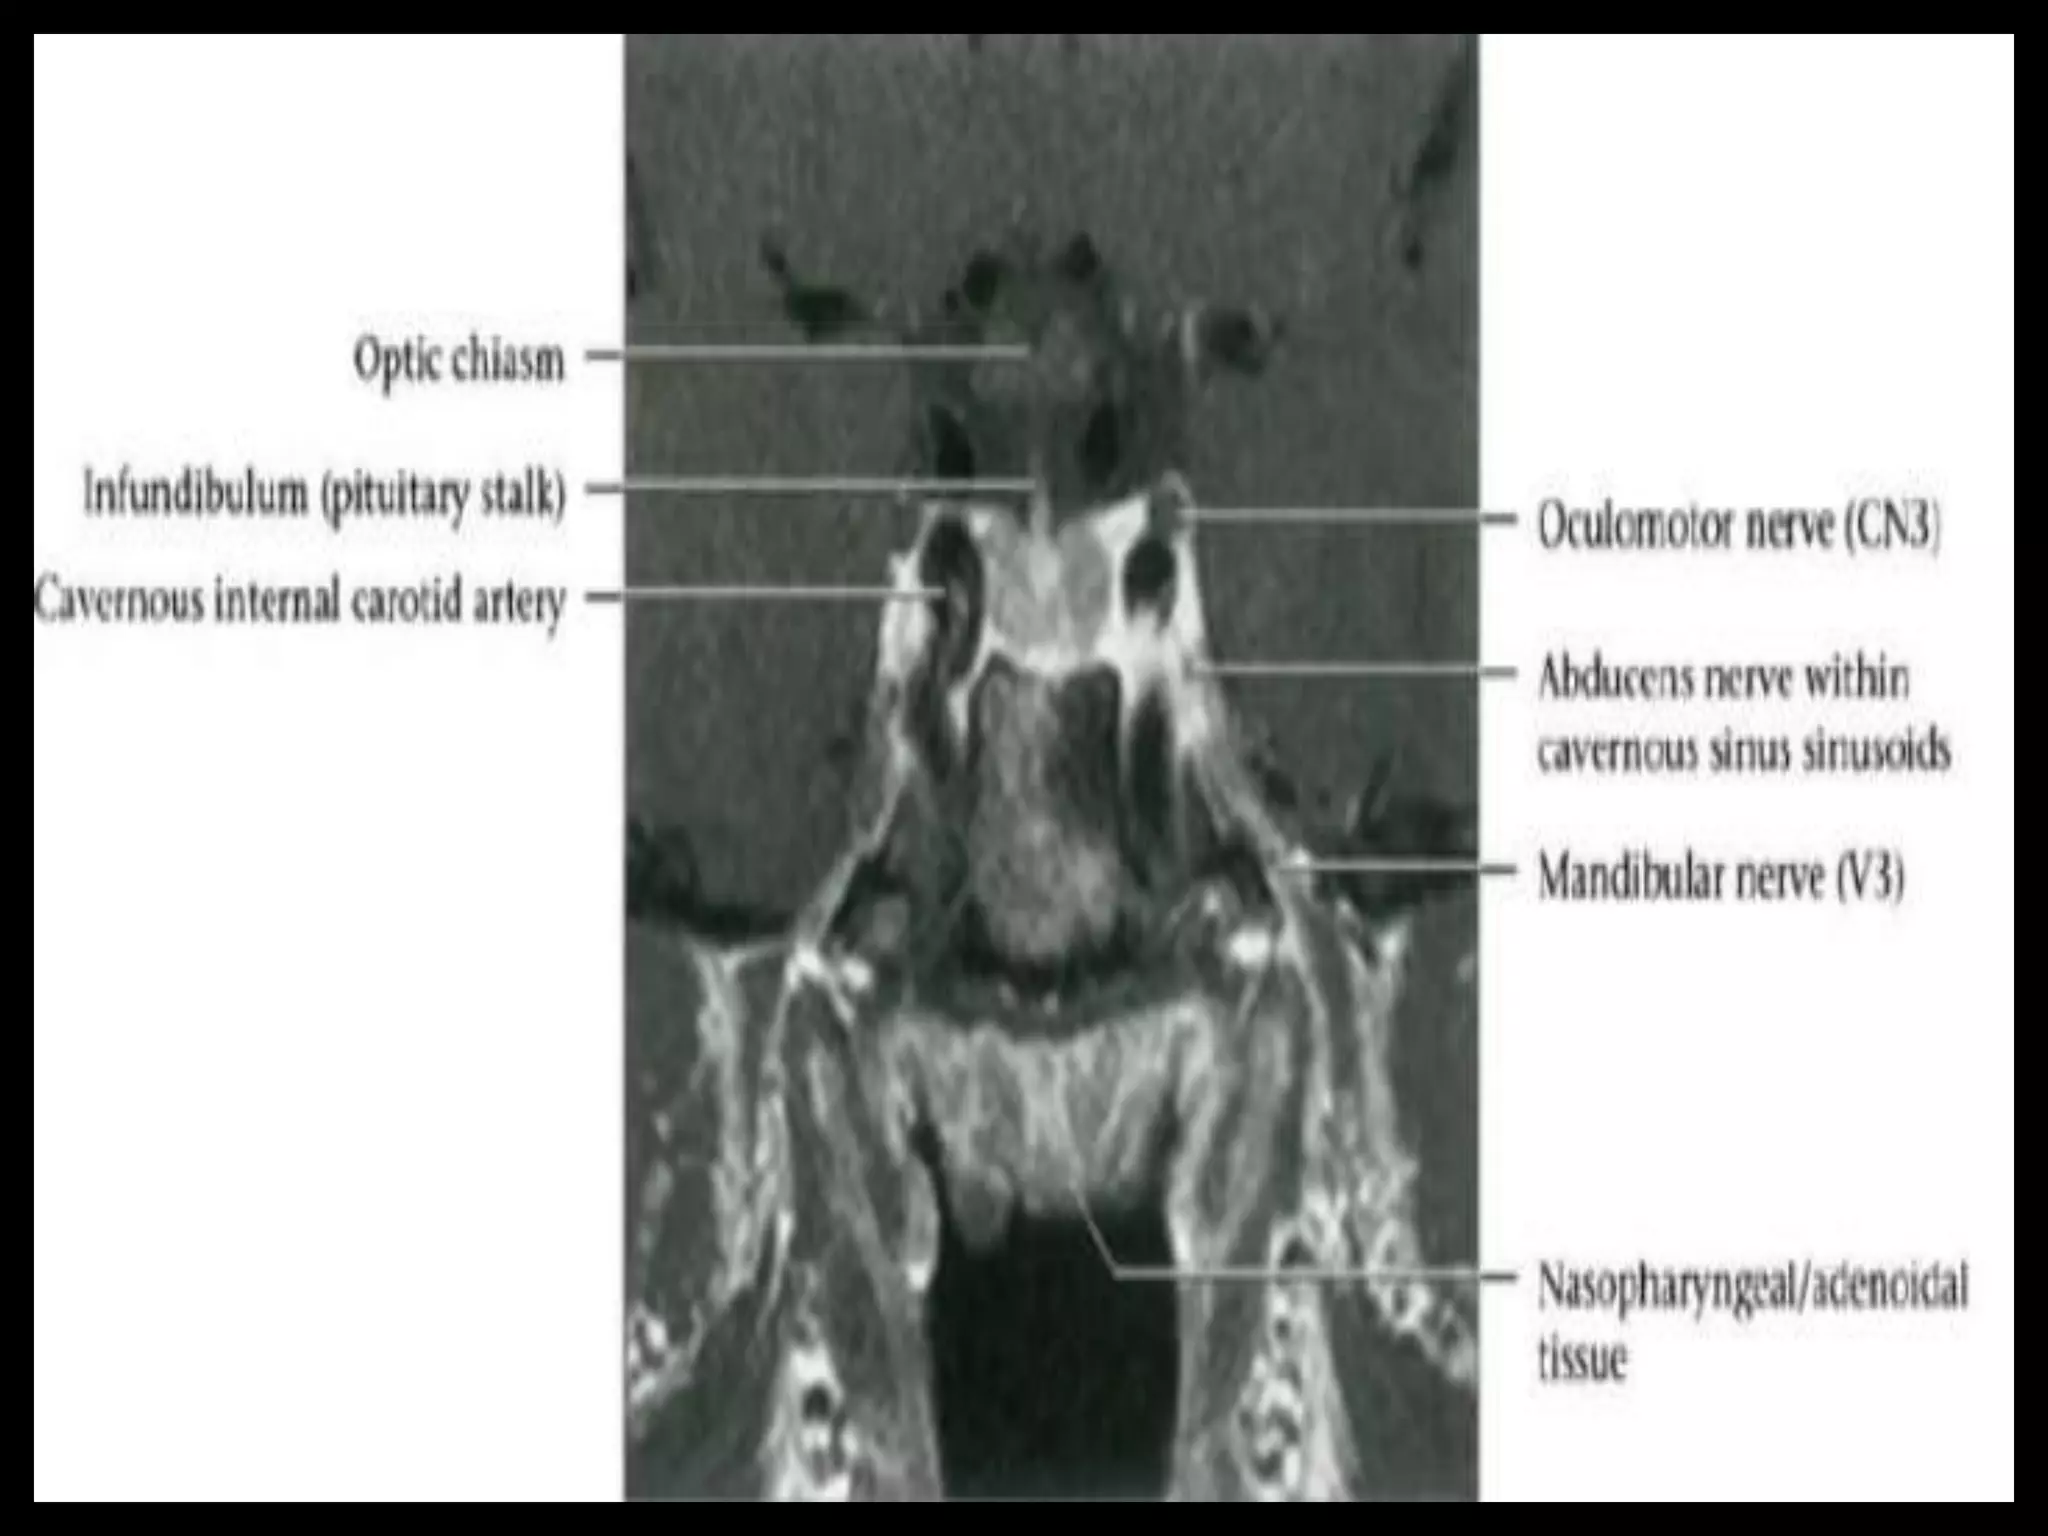

Suprasellar Cistern

And Optic Apparatus.

Suprasellar Cistern AndOptic Apparatus.